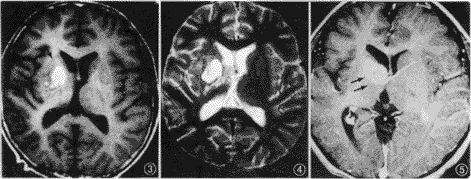

四、瘤旁水肿与肿瘤扩散:位于基底节的9例中,8例见肿瘤旁有轻微水肿带,1例无瘤旁水肿;2例位于丘脑者未见明显瘤旁水肿。9例位于基底节的肿瘤中,4例见肿瘤向对侧基底节扩散(图6)。位于丘脑的2例中,无一例向对侧扩散。

五、占位征象与同侧皮层萎缩: 基底节及丘脑生殖细胞瘤占位征象多不明显,其中5例基底节生殖细胞瘤可见同侧大脑皮层萎缩征象,表现为外侧裂及脑沟增宽(图7)。

图6 右侧基底节生殖细胞瘤。增强扫描见 图7 同侧大脑皮层萎缩(箭头与

肿瘤向对侧扩散(箭头) 图3~5为同一病人)